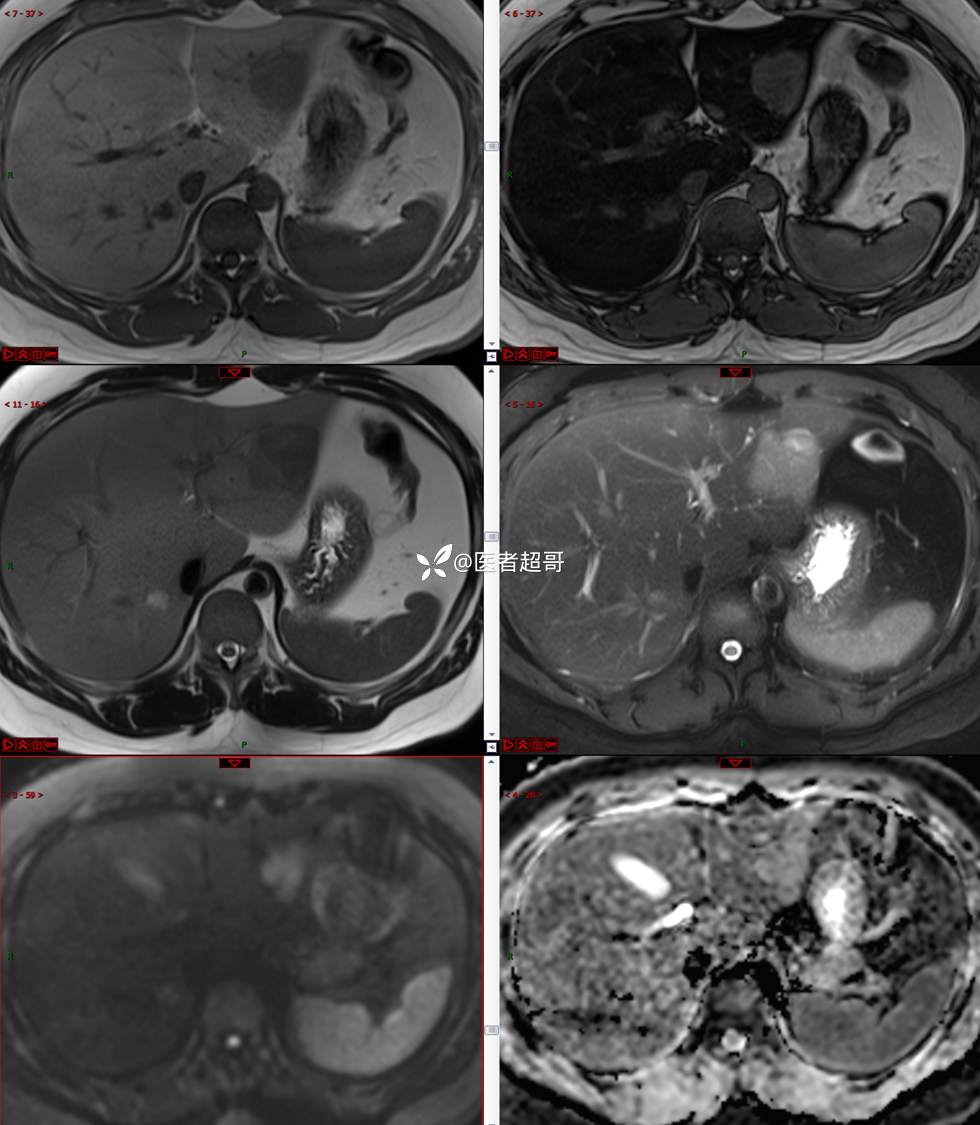

【影诊笔记800】青年男性,肝脏占位,特殊对比剂提示富血供,您能想到啥?有结果!

男,31y

主 诉:发现肝占位性病变5天。

现病史:患者缘于5天前体检时发现肝占位性病变,未予以特殊处置。现患者为求系统诊治就诊于我院,行普美显提示:肝左叶富血供占位,请结合临床及其他检查,肝多发血管瘤,脂肪肝,肝囊肿,请结合临床。门诊以“肝占位性病变”收入我科。病程中,饮食睡眠可,二便可,近期体重未见明显变化。